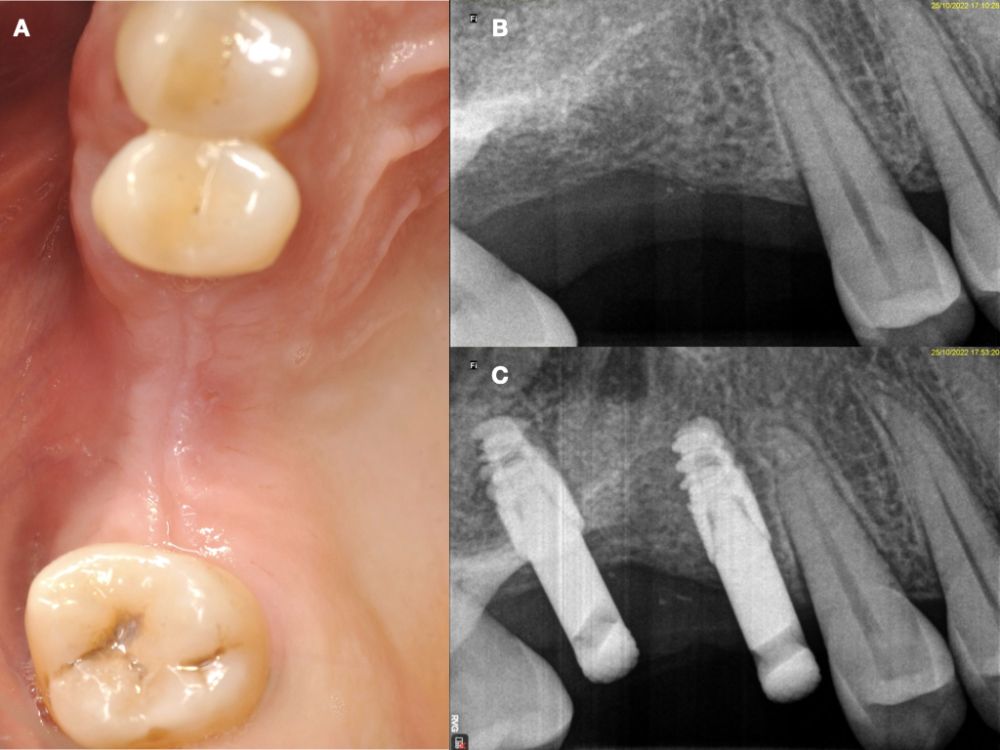

En la historia clínica, no se evidenciaron antecedentes médico-quirúrgicos de interés, alergias medicamentosas conocidas ni hábitos nocivos. A la exploración intraoral, se apreciaron las ausencias de 1.6 y 1.7 y la presencia del 1.8 y 4.8 (Figura 1). En la exploración radiográfica mediante escáner de haz cónico (CBCT) se apreció una altura residual de 5,0 mm en 1.6, donde se podría colocar un implante simultáneo, y de 2,6 mm en la zona del 1.7, dificultando la colocación de un implante de manera simultánea a la elevación de seno de acceso lateral (Figura 2).